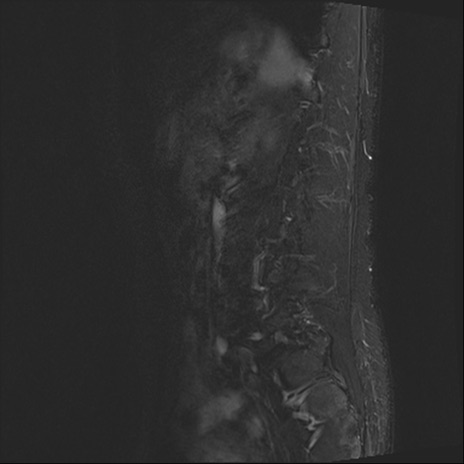

【整形】TIPS症例4 腰椎MRI STIR(矢状断像)

腰椎MRI